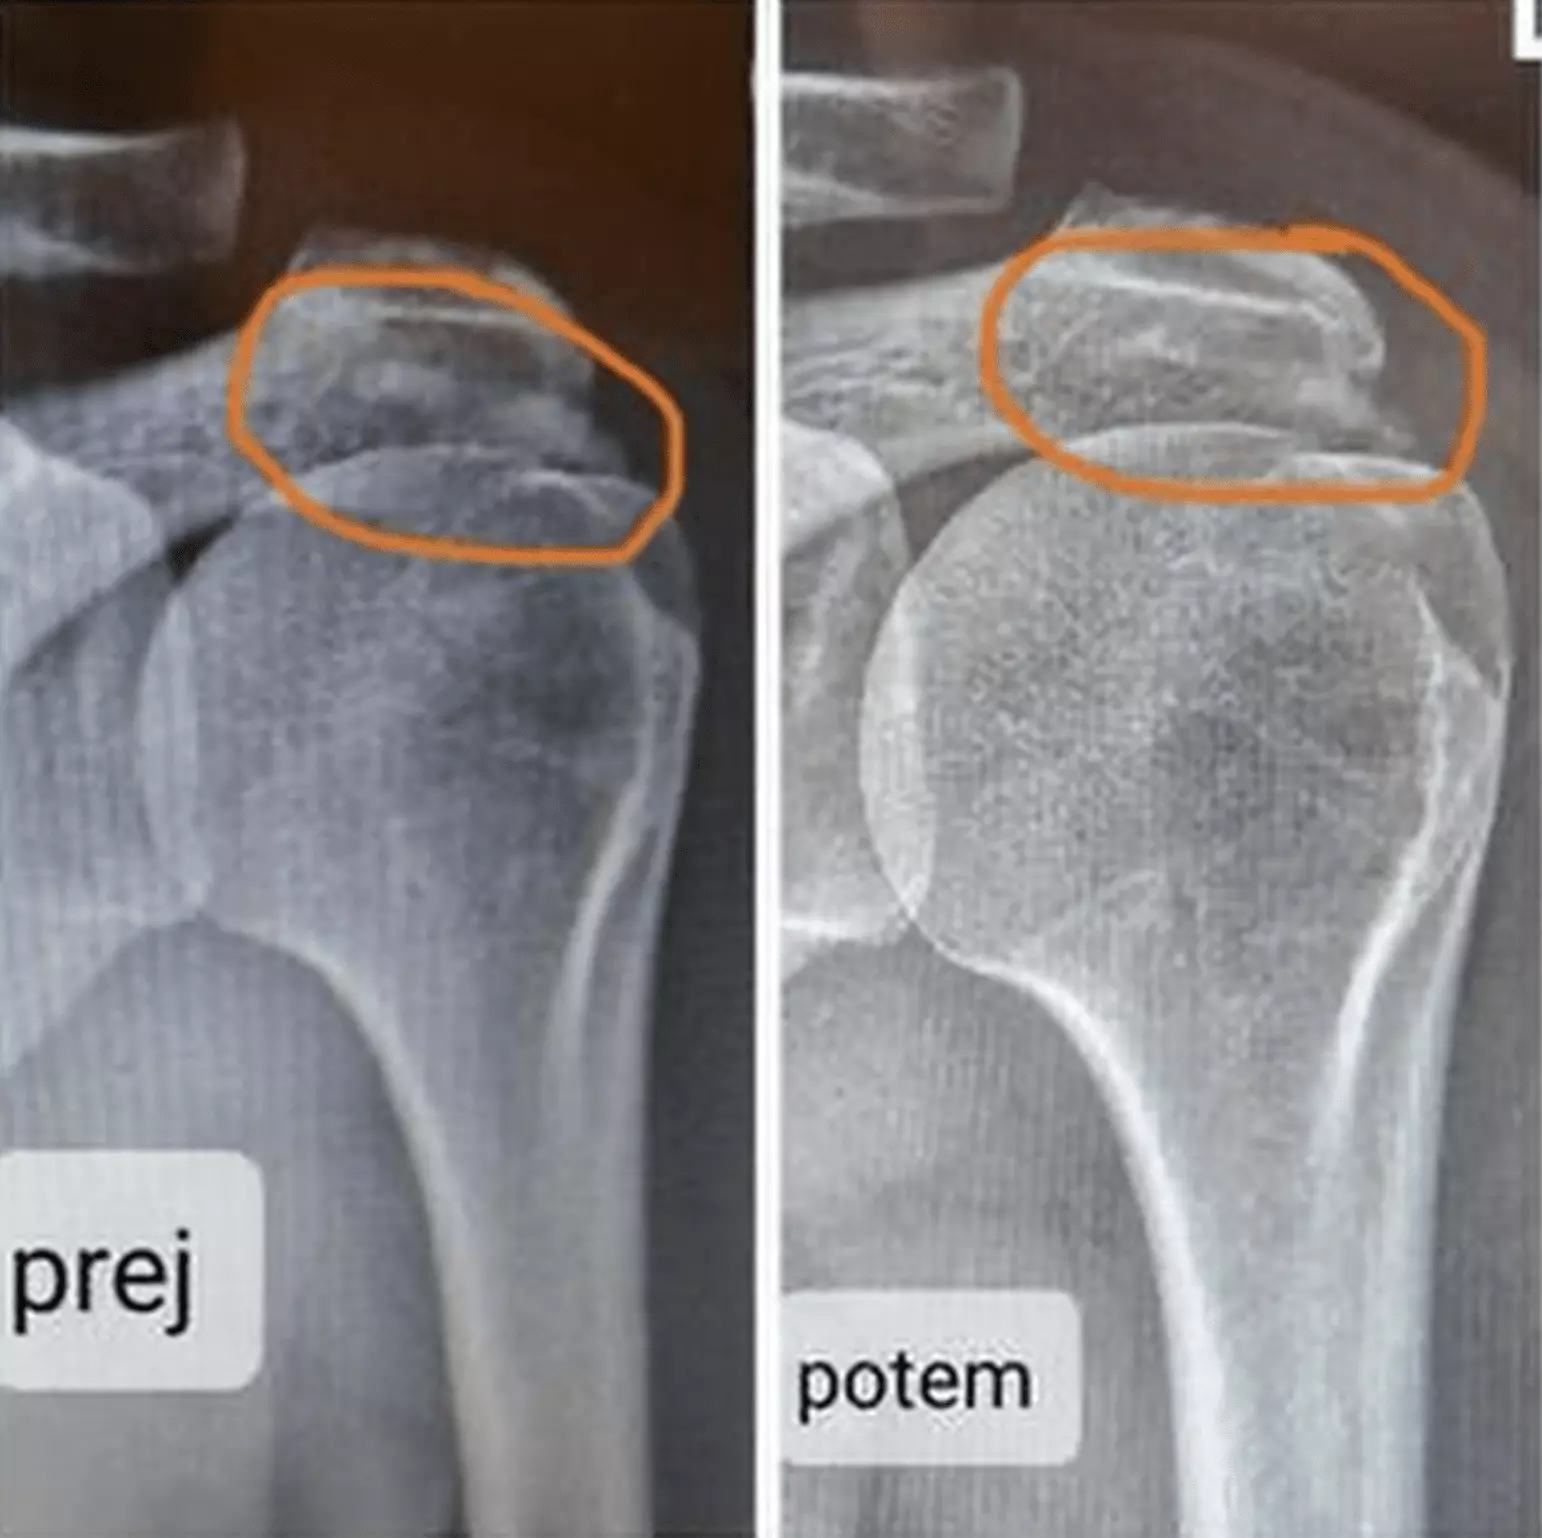

Bolečine v kolenu

Naši strokovnjaki fizioterapije vam bodo pomagali pri bolečinah v kolenu, ki so povezane z naslednjimi poškodbami.

• Poškodba meniskusa (vnetje, pok, ruptura)

• Ruptura medialnega meniskusa

• Bakerjeva cista

• Ruptura sprednje križne vezi (ACL)

• Gonartroza

• Hondropatija

• Tekaško in skakalno koleno

• Zvin in izpah kolena

• Artritis kolena

• Burzitis kolena

• Izpah kolena

• Izpah pogačice